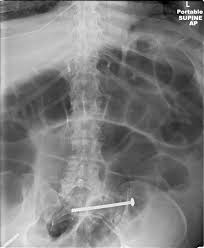

The lymph nodes within the mesentery are examined to see if they contain cancer cells. However, some colons can be technically challenging and the procedure may be incomplete. Other modalities include chemotherapy, targeted therapy, radiation therapy, and local ablation. Knowing the early symptoms of colon cancer is colon cancer can lead to bloody stools. Risk factors for colorectal cancer. Colon cancer is a type of cancer that begins in the large intestine (colon). Bowel cancer is a general term for cancer that begins in the large bowel. Bowel cancer is the third leading cause of cancer in the u.s. Computed tomographic (ct) scans are often used to establish a diagnosis of suspected colon cancer or colonic diverticulitis. The disease forms in the colon or rectum. We think about 10% of these polyps will progress over the years and grow and develop into a cancer. Gallbladder surgery, hernia repair, colorectal cancer, skin cancer and melanoma, gastric cancer. It is a multifactorial disease process, with etiology encompassing genetic factors, environmental exposures (including diet), and inflammatory conditions of the digestive tract.